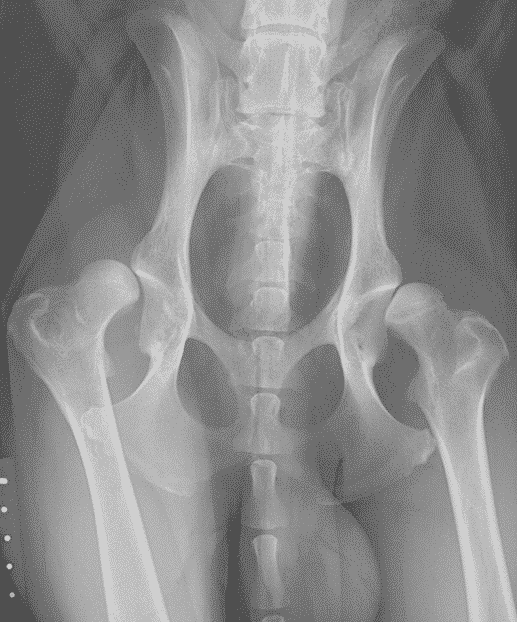

Even though there is limited association between radiographic and clinical signs of dysplasia, when both are severe, dogs are likely to benefit from early total hip replacement (Figures 1 and 2). In young dogs, the typical example is an eight- to nine-month-old medium to large-breed dog with luxoid hips which cannot walk for more than 10 to 20 minutes (Figure 2). These patients often only partially respond to conservative management and waiting for too long before a total hip replacement surgery may compromise its outcome. These dogs may experience remodelling of their proximal femoral metaphysis and diaphysis which may preclude the use of conventional implants or the chronically luxated hip may be extremely challenging to reduce in the future.